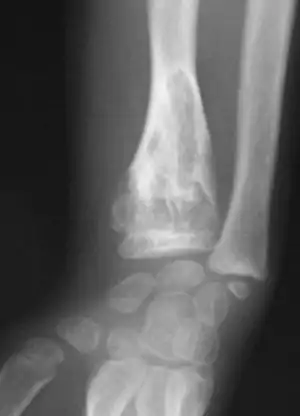

X-ray showing enchondromas localized in the humerus of a 37-year-old patient affected with Ollier disease